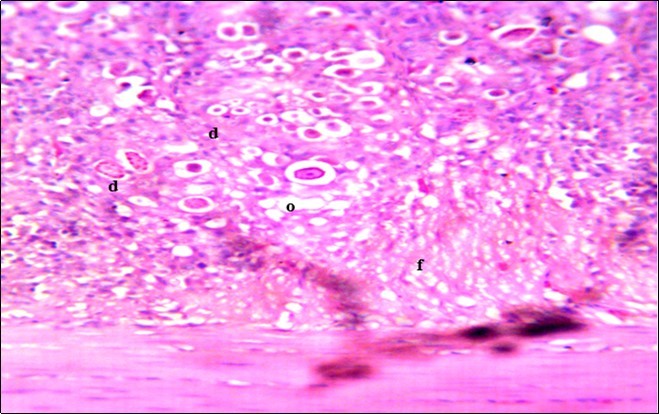

In this study, the reduction in oocyst count observed in the treated group was compared with amprolium could be attributed to the presence of a bioactive compounds azadiractin A which is known to bind membrane cholesterol, altering the integrity of the parasite membrane, resulting in loss of homeostasis and eventual death of the parasite 29]. Also, limonoids contained in NeemAzal® inhibit protein digestion and uptake of vitamins and minerals by the parasites in the gut 17. This action results in impaired nutrient utilization, reduced growth, and multiplication of the parasite which could contribute to the reduced oocyst count observed. Extracts of neem and mahogany when used individually have been reported to reduce oocyst count in avian coccidiosis 11,12. The observed reduction in oocyst count and the significant increase in weight gain of the birds when treated with NeemAzal®, as compared with the negative control group could probably be due to the inhibition of inflammation in the intestinal mucosa which is suggestive of an increased nutrient absorption across the intestinal wall and enhanced feed conversion ratio compared to the negative control this is in agreement with reports by Nwosu et al.12 and Biu et al.11 who also reported an increased weight gain and feed conversion ratio in birds treated with only Khaya senegalensis extracts and Azardiractaindica, respectively. The observed increase in RBC and haemoglobin concentration is indicative of the erythropoieticability of the NeemAzal®, which is beneficial since the Eimeria parasite in the epithelia of the intestines causes bloody diarrhoea and consequently anaemia (Table 1). This finding is in consonance with 15 who reported an anti-anaemic effect of Khaya Senegalensis on phenyl hydrazine-induced anaemia in rats. Neem has been shown to possess anti-anaemic properties in rats 14. The significant increase in mean weight gain in treated birds when compared to the negative control is possibly due to the inhibition of inflammation in the intestinal mucosa which is suggestive of an increased nutrient absorption across the intestinal wall and enhanced feed conversion ratio compared to the negative control. Nwosu et al.12 and Biu et al.11 reported an increased weight gain and feed conversion ratio in birds treated with only Khaya Senegalensis andAzadiractaindica extracts, respectively. In a similar study, Neem acts like toltrazuril exhibiting anticoccidial. In addition, exposure of broiler chickens to 20000 Oocysts of Eimeria tenellacaused generalized degeneration of the caecal glands with massive Oocysts and gametocyts within the caecal glands with fibrosis (Figure 3, Figure 4 & Figure 5), however, broiler chickens treated with NeemAzal® post exposure to 20000 Oocysts of Eimeria tenella, shows equal numbers of caecal tissues with non-observable histopathological lesions (Figure 4), possibly due to the antioxidant and anti-coccidian effects of NeemAzal®. The exact mechanism of action of neem against coccidian parasites is unknown, but a report by the National Research Council 1992 30, suggested that aqueous neem leaf extract, when taken orally, produces an increase in red cells, white blood cells and lymphocyte counts thus enhancing the cellular immune response, increasing antibody production and so most pathogens can be removed before they cause the symptoms associated with disease this was in agreement with this study as seen in Table a remarkable increase of the RBCs.

Figure 4.Photomicrograph of caecum of chick administered 20000 Oocysts of Eimeria tenella and untreated showing generalized degeneration of the caecal glands (d) with massive Ocysts (o) and gametocytes (g) largely within the caecal glands X250 (H&E).

Figure 5.Photomicrograph of caecum of chick administered 20000 Oocysts of Eimeria tenella and treated with NeemAzal® Oil showing generalized degeneration of the caecal glands (d), moderate Ocysts presence (o) with fibrosis (f) X250 (H & E).